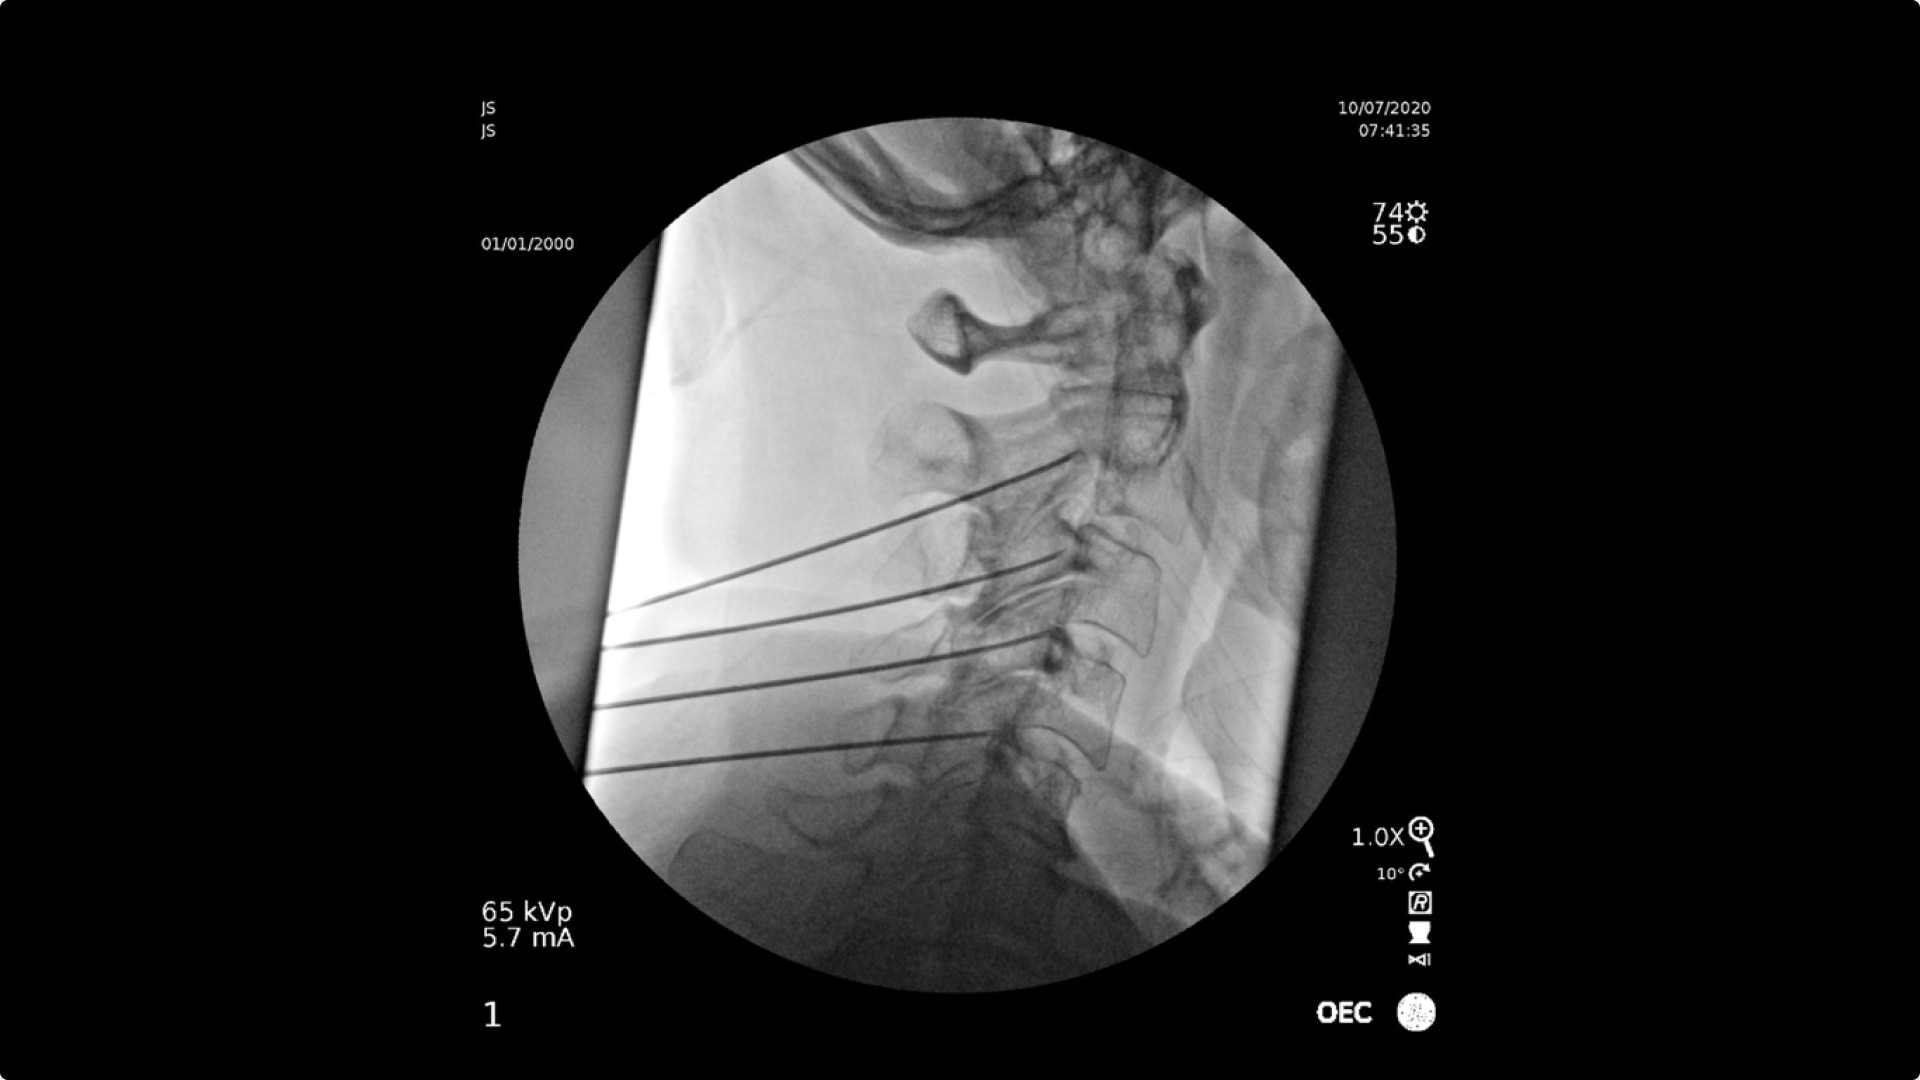

See clear detail captured on a flat panel detector to a 4K display for visualization of anatomical detail.

Live Zoom up to 4Xs to see needle placement, without the use of Mag mode. Live Zoom also enable panning to an area of interest without having to move the base of the C-arm.

OEC C-arms perform imaging in a variety of procedures such as:

• Cervical spine pain management